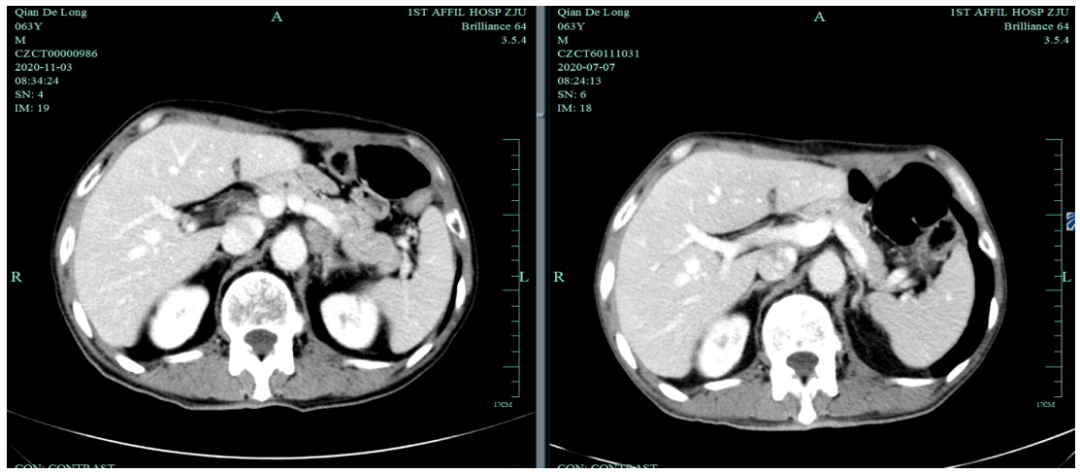

入我院后全面进行评估(2019.4):全腹部CT平扫+增强评估提示腹膜后,胰腺周围多发淋巴结增大,淋巴结转移考虑。

末次化疗时间为2020-7-6,定期复查于2020-11发现标记物明显升高,影像学提示疾病进展。

2020-11-3全腹部CT平扫+增强提示胃癌术后改变,术周及腹膜后多发肿大淋巴结显示,对照2020-7-7CT淋巴结肿大进展,结合临床疗效评估PD。